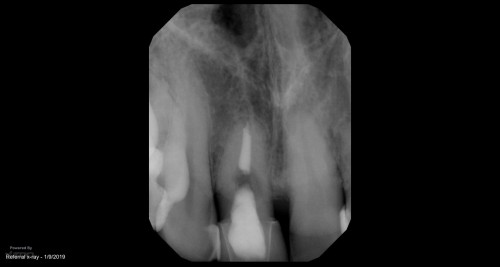

#15 (?) Routine endo

Calcified canals are never an excuse under the scope. This #15(?) was in the position […]